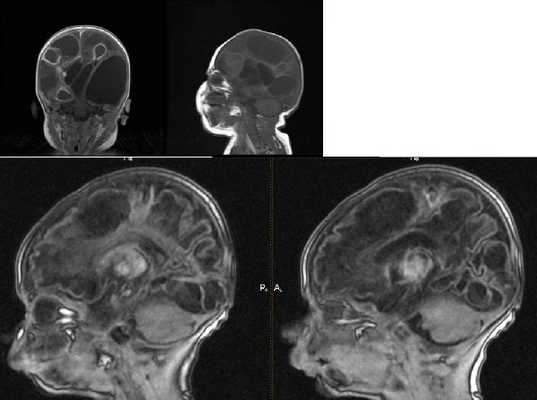

Мультикистозная энцефаломаляция: причины, симптомы, диагностика

Множественные кистозные полости в разных частях головного мозга у новорожденных встречаются часто. Большинство видов не представляет опасности, так как проходят самостоятельно к году. Крупные мультикисты вызывают энцефаломаляцию из-за захвата большой части мозговой паренхимы, полушарий.

Энцефаломаляция у новорожденного МРТ

Диагностика лейкомаляции

Определить нозологию сразу после рождения помогает клиническая картина. Выявление любого признака требует подтверждения методами нейровизуализации. Компьютерная, магнитно-резонансная томография (КТ и МРТ) помогают обнаружить все изменения церебральной паренхимы. Нарушение кровоснабжения верифицируются контрастными обследованиями - ангиография.

Энцефаломаляция на КТ визуализируется при наличии средних и крупных кист с рубцовой стенкой. Дифференциальная диагностика с помощью МР-ангиографии позволяет верифицировать первичную мультикистозную энцефаломаляцию головного мозга от эхинококковых и альвеококковых полостей.

У новорожденных роднички представлены хрящевой тканью. До полного зарастания изучать церебральные структуры ребенка позволяет УЗИ или МРТ головного мозга.